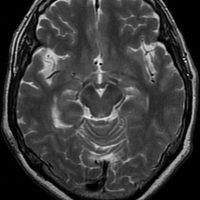

最も多いタイプで50%くらいです。7歳の子に偶然発見された右シルビウス裂のくも膜のう胞です。大きいのですがこの程度では治療の必要はありません。シルビウス裂のくも膜のう胞は最も多いものです。